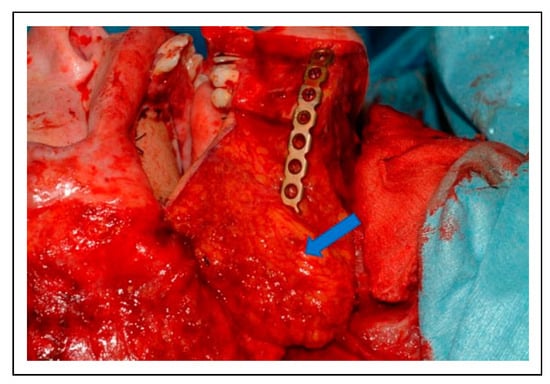

Figure 13. A 3D reconstruction plate was used to bridge the segmental defect in the mandible and then covered with the fascial extension flap (arrow) that was placed over the plate to protect the overlying skin. The palatal and buccal reconstruction is demonstrated.

A staged approach was adopted in order to address the patient’s multitude of problems. At the initial surgery, a segmental mandibular resection and coronoidectomy were performed. The bony mandibular defect was bridged with a 3D reconstruction plate. During this procedure, the central palatal defect was reconstructed with a radial forearm flap that sealed the palate and restored the mucosa of the right cheek and floor of mouth (Figure 12). A subcutaneous fascial extension of the radial forearm flap was placed over the reconstruction plate to protect the thinned, radiated facial skin (Figure 13).